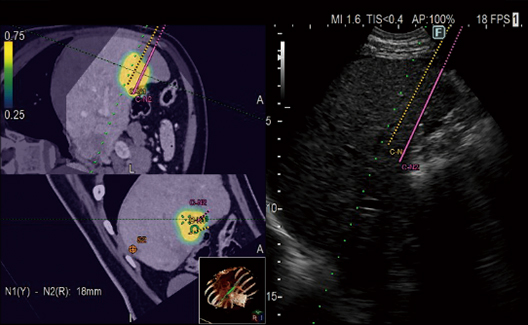

Provides simulation of single or multiple needle paths during navigation to a target with Real-time Virtual Sonography (RVS). The positional relationship between the marked target and needle paths can be assessed in real time using the 3D body mark, reconstructed from the virtual CT volume data, with additional C-plane display orthogonal to the needle path.

A color map superimposed on the CT image simulates the distribution of the electric field (E-field) from the given location of multiple electrodes during RFA treatment. The simulation can be made with different positions of the multiple electrodes to determine the optimal arrangement. This flexibility in planning the needle path can bring significant improvement to the treatment technique.